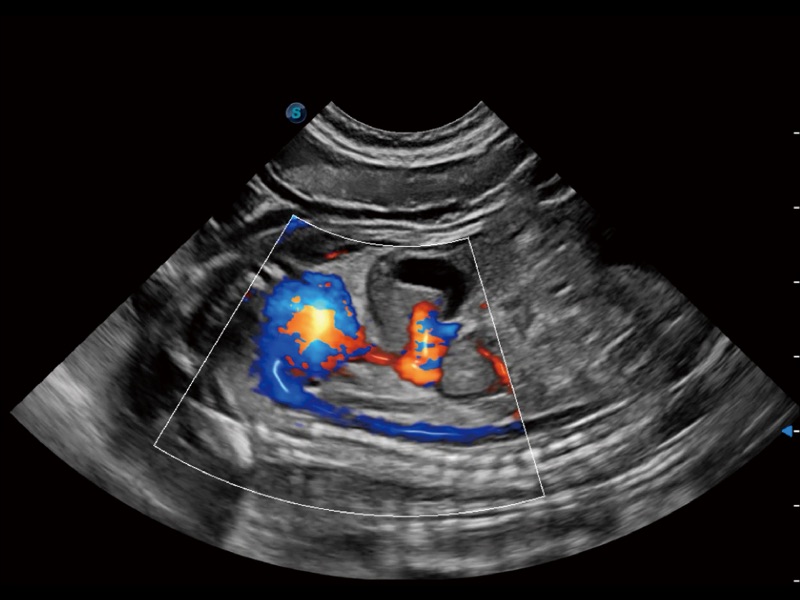

优异的基础图像

ProPet 70 全新的动物超声智能软件和丰富的探头群,为动物医生提供了高清晰度和精细分辨率的图像,无论在宠物、马科、畜牧还是实验室动物等应用中都可以轻松应对,为您的日常工作带来满意的体验。

(犬)左室长轴血流